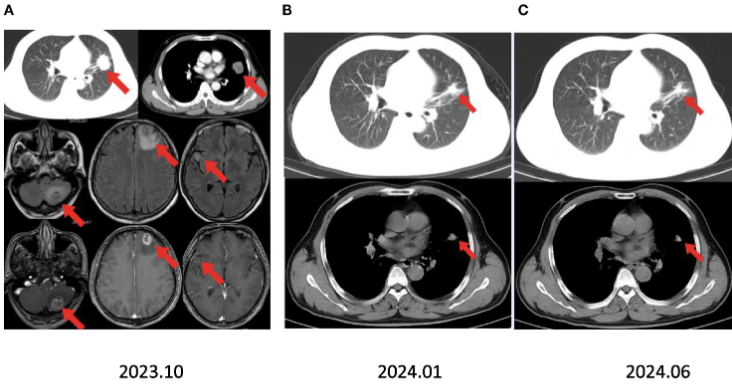

疗效评估

术后继续予伏美替尼辅助治疗,随访至2025年5月(术后18个月),头颅MRI示无复发灶,肺部及脑部均未发现肿瘤复发。